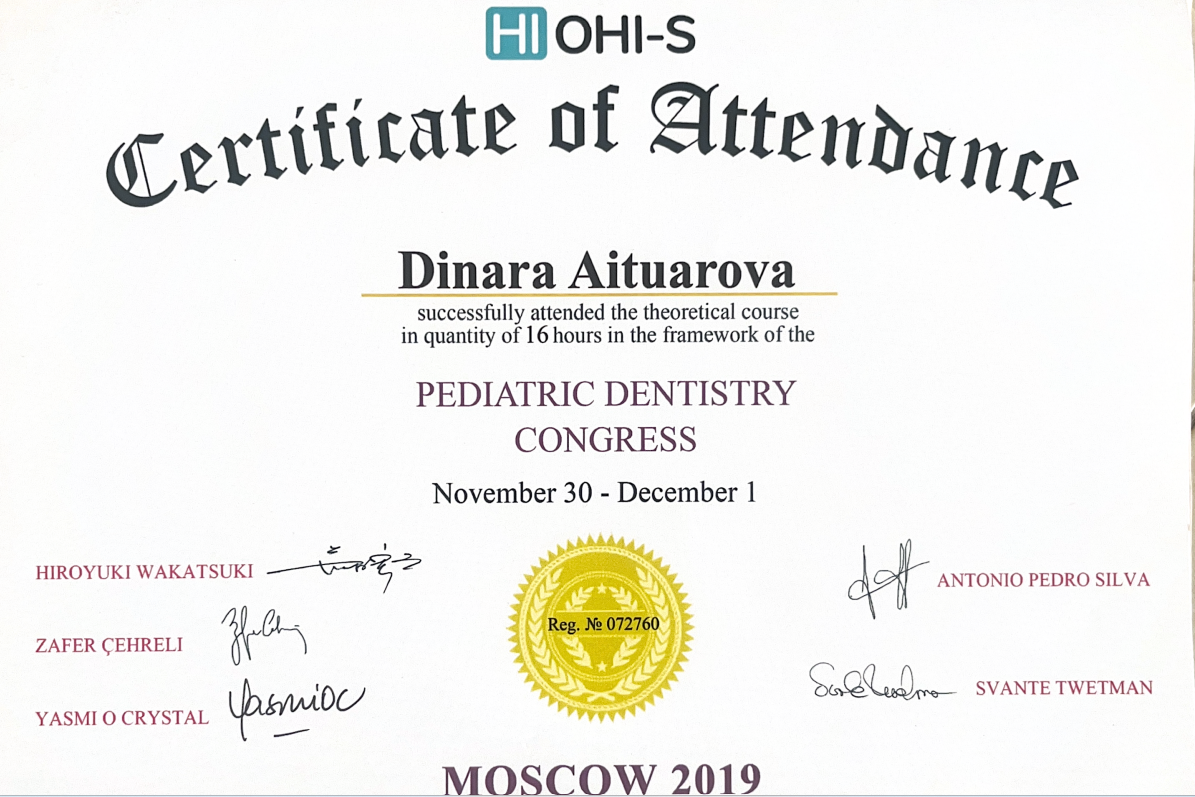

Айтуарова Динара Тахиржановна

Практикующий врач-стоматолог с более чем 23-летним стажем.

Обучается новым технологиям и внедряет современные методы в практику